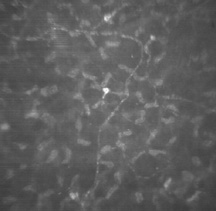

KERATOCYTES

Occupying 3% to 5% of the total stromal volume, keratocytes are interspersed throughout the corneal stroma and form a communicating network through their branching stellate processes. With confocal microscopy, keratocytes appear to be less densely dispersed than in Bowman's layer (Fig. 15). In the deep stroma, keratocytes appear spindle-shaped and more numerous than in the midstroma (Fig. 16).

Fig. 15. Confocal microscopic transverse image of the human mid-stroma in vivo. The keratocyte nuclei appear less dense than in Bowman's layer and less refractile. Note the highly refractile nucleus in the upper part of the image. This may be an activated keratocyte (500×). (Courtesy of Nidek Technologies.)

Fig. 16. Confocal microscopic transverse image of the human deep-stroma in vivo. Many of the keratocyte nuclei at this level are spindle-shaped and appear dense in numbers compared to the central cornea (500×). (Courtesy of Nidek Technologies.)